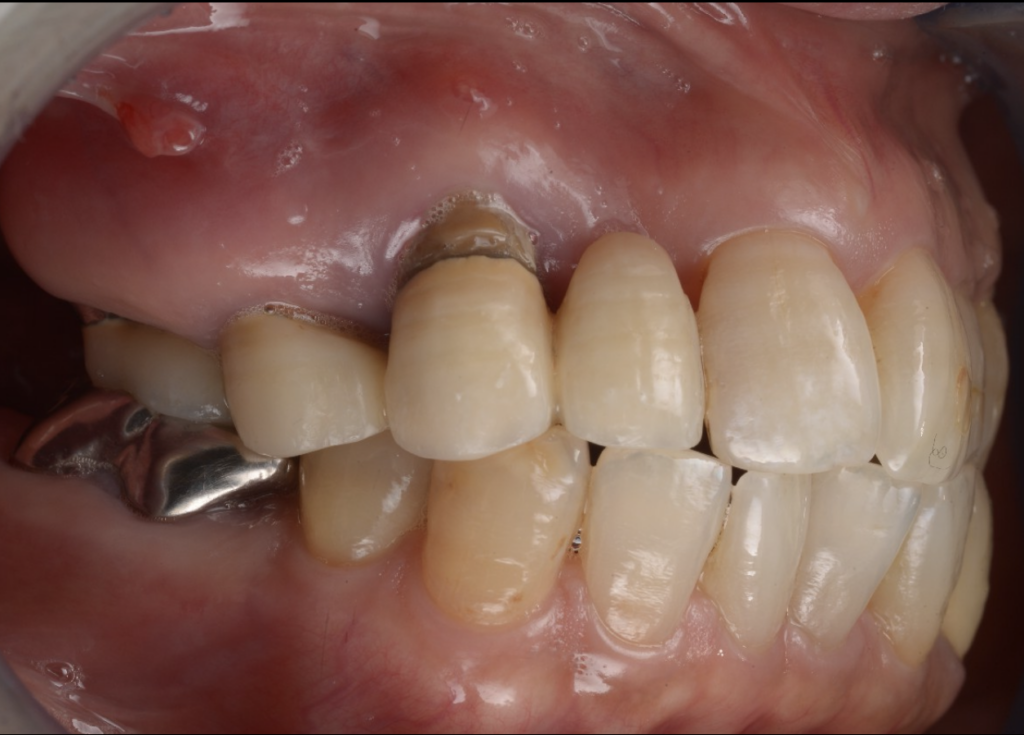

今回ご紹介するのは、噛み合わせに無理がある補綴設計が背景となり、腫れ・動揺が進行して日常の食事にも支障が出ていた患者様のケースです。

なぜ「膿む・グラグラする」「噛めない」まで進んだのか

歯が腫れたり動いたりする原因はさまざまですが、再治療で重要なのは

“なぜ壊れたのか”を力のかかり方から見直すことです。

補綴設計や噛み合わせに無理があると、特定の部位に負担が集中し、

- 炎症(腫れ・排膿)

- 動揺(グラつき)

- 噛むと痛い/噛めないといった状態に進行することがあります。

治療の工夫②:上下ともにインプラントブリッジで機能を回復

上下ともにブリッジ設計とすることで、噛む機能を回復しながら

設計の自由度と安定性を確保しました。